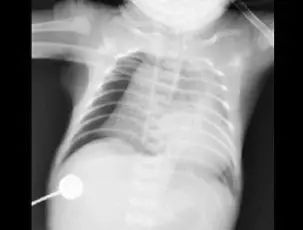

7月29日,原本身体很好的豆豆,不知为什么总会连续咳嗽,甚至嗓子都出现了沙哑,还突然出现哮喘,气促、呼吸困难等症状。在医院做完检查后,而胸片的结果却让在场所有人震惊:孩子的左肺竟然“不见了”?!

肺从片子上消失,医学上称为“白肺”。正常的肺部有空气进入,在 CT片上是呈影的。“白肺”,即肺部显影呈一大片的白色状,起因一般是重症肺炎或者大量的胸腔积液。但是豆豆并没有肺部疾病史,究竟是什么原因呢?